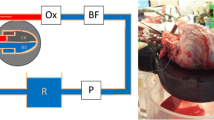

Pelgrim GJ, Duguay TM, Stijnen JM et al (2017) Analysis of myocardial perfusion parameters in an ex-vivo porcine heart model using third generation dual-source CT. J Cardiovasc Comput Tomogr 11(2):141–147

Pelgrim GJ, Das M, van Tuijl S et al (2017) Validation of myocardial perfusion quantification by dynamic CT in an ex-vivo porcine heart model. Int J Cardiovasc Imaging 33(11):1821–1830

Hubbard L, Lipinski J, Ziemer B et al (2018) Comprehensive assessment of coronary artery disease by using first-pass analysis dynamic CT Perfusion: validation in a swine model. Radiology 286(1):93–102

George RT, Jerosch-Herold M, Silva C et al (2007) Quantification of myocardial perfusion using dynamic 64-detector computed tomography. Invest Radiol 42(12):815–822

Bamberg F, Hinkel R, Schwarz F et al (2012) Accuracy of dynamic computed tomography adenosine stress myocardial perfusion imaging in estimating myocardial blood flow at various degrees of coronary artery stenosis using a porcine animal model. Invest Radiol 47(1):71–77

So A, Wisenberg G, Teefy P et al (2018) Functional CT assessment of extravascular contrast distribution volume and myocardial perfusion in acute myocardial infarction. Int J Cardiol 266:15–23

So A, Hsieh J, Li JY, Hadway J, Kong HF, Lee TY (2012) Quantitative myocardial perfusion measurement using CT perfusion: a validation study in a porcine model of reperfused acute myocardial infarction. Int J Cardiovasc Imaging 28(5):1237–1248